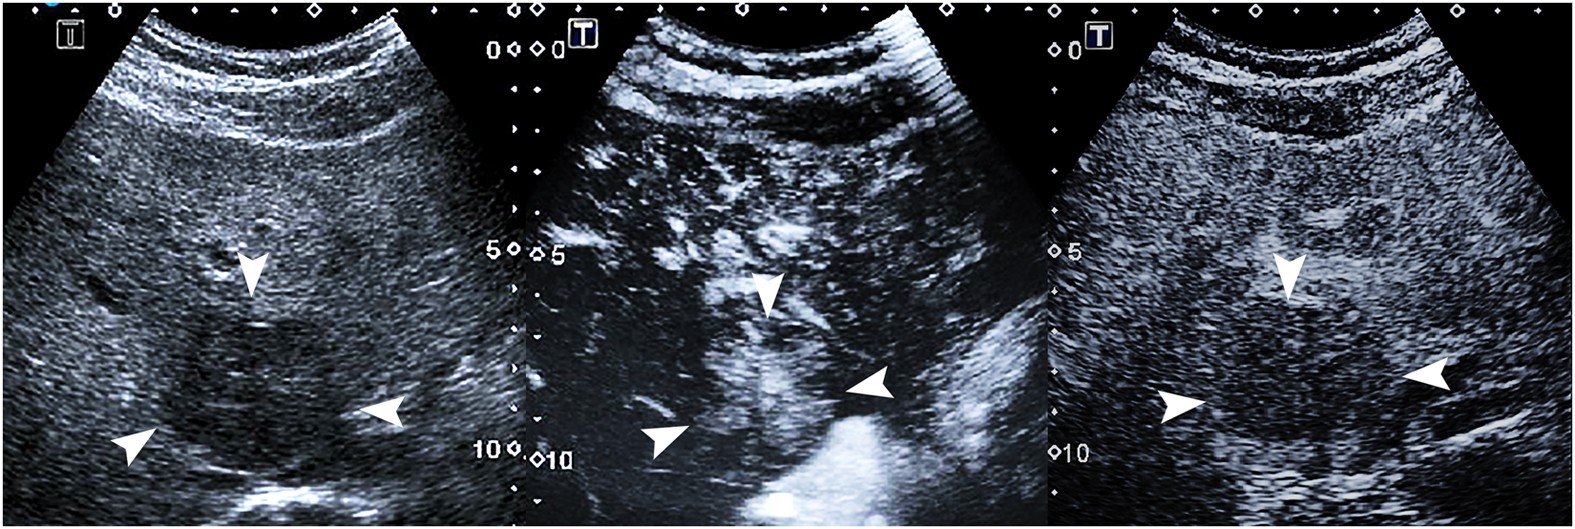

Figure 4

Focal nodular hyperplasia in a 29-year-old man.

(a) A 5.4-cm lesion (arrows) in the liver shows hypoechogenicity on conventional ultrasound. (b) Contrast- enhanced ultrasound shows spoke-wheel arteries (arrow) in the lesion 12ās after contrast agent administration. (c) The lesion (arrows) shows hypoenhancement in comparison with adjacent liver tissue 69ās after contrast agent administration.